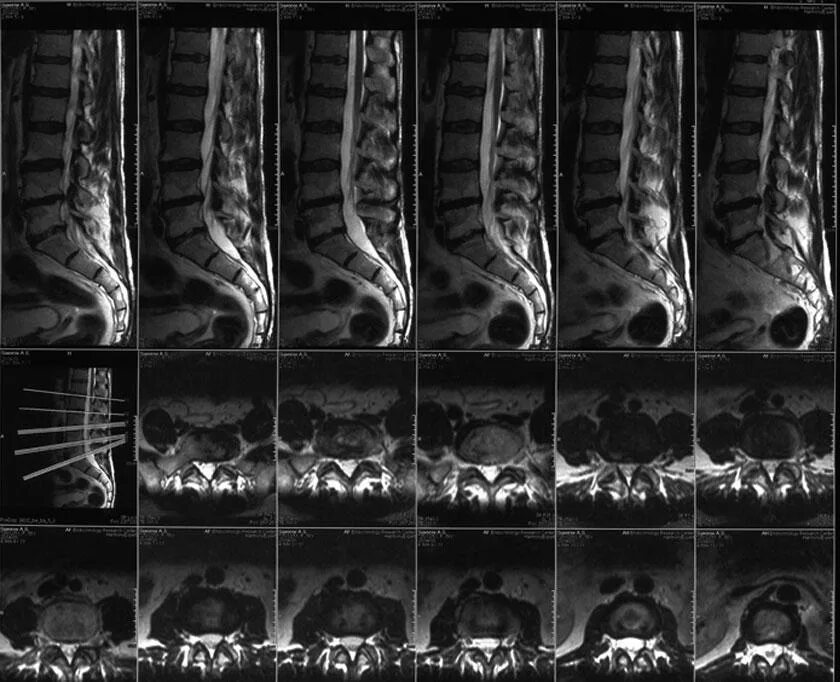

Мрт поясничного отдела подготовка к процедуре